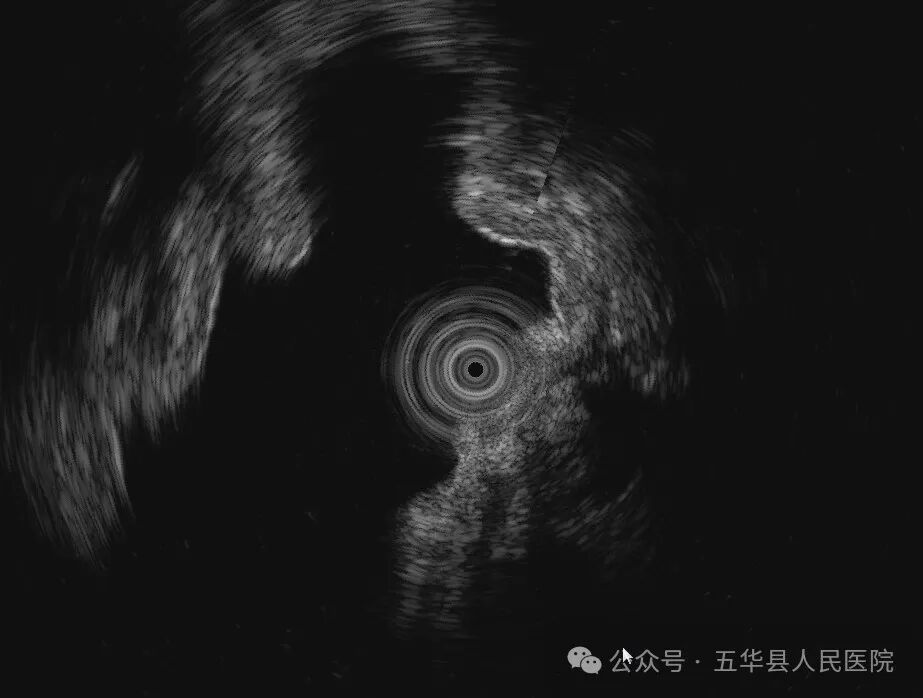

据悉,该患者为老年女性,长期上腹部不适,近期患者症状加重,来我院行胃镜检查发现胃底黏膜下隆起,胃多发息肉。胃黏膜下隆起可能是胃肿瘤如间质瘤、平滑肌瘤、神经内分泌瘤等,也可能是胃壁外血管或脏器压迹,需要行超声内镜检查加以鉴别,为下一步治疗奠定基础。既往我县无超声内镜设备及技术,此类患者需要前往市医院接受检查。我院超声内镜检查的成功开展,标志着五华县内镜诊疗进入新的发展阶段。

超声内镜是将微型高频超声探头安置在内镜顶端,就像是给内镜开启了“透视”功能。在内镜直接观察消化道黏膜病变的基础上,利用超声实时扫描,可获得检查脏器及周围邻近脏器的超声图像,“透视”人体管腔的层次结构、病变起源和浸润深度,甚至是周围邻近脏器的组织结构也一览无遗,真正意义上实现了消化系统疑难疾病的精准诊断。